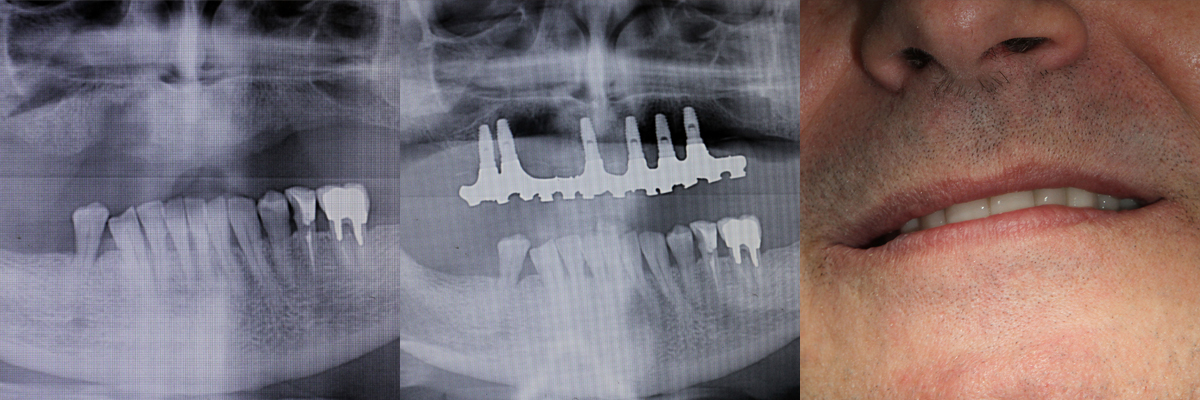

Lavoro eseguito nel 1993

Impianto elementi superiori